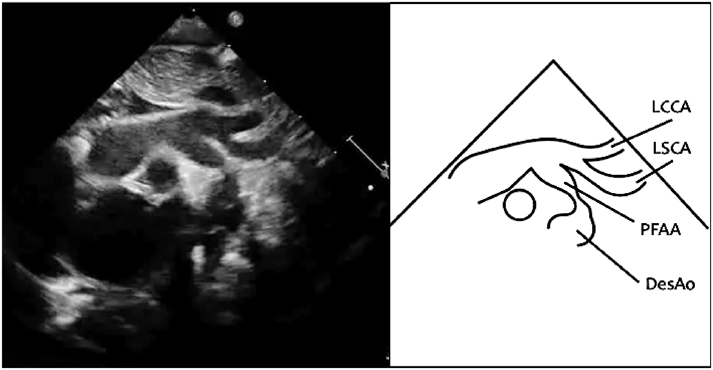

第5大動脈弓遺残に第4大動脈弓離断を合併した大動脈縮窄の2手術例Successful Repair of Coarctation of the Aorta Using Fifth Aortic Arch in Two Neonates with the Persistent Fifth Aortic Arch and Interrupted Fourth Aortic Arch